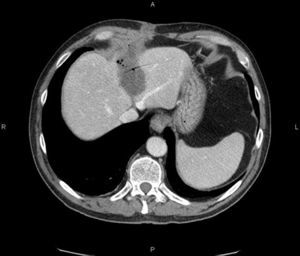

Varón de 70 años con antecedente de hidatidosis duodenal intervenida hace 30 años, que consulta por tumoración dolorosa en cicatriz de laparotomía. Durante una cura se abre espontáneamente y supura material seroso e hidátides. Una ecografía y una TC abdominal revelan una colección de contenido hipodenso en segmento hepático V, fistulizada a piel (figs. 1 y 2). Se explora quirúrgicamente la herida y se coloca drenaje multiperforado (fig. 3, flechas: hidatides). Se administra albendazol y se realizan lavados con suero salino hipertónico durante 2 semanas hasta la resolución clínico-radiológica del cuadro. El estudio microbiológico fue negativo y la anatomía patológica confirmó el diagnóstico de hidatidosis.